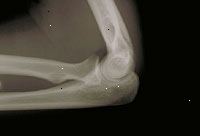

Χ-Χ του αγκώνα

Ένα X-ray μπορεί να πραγματοποιηθεί σε μια βάση εξωτερικών ασθενών ή ως μέρος της διαμονής σας σε ένα νοσοκομείο. Διαδικασίες μπορεί να διαφέρουν ανάλογα με τη νόσο σας και τις πρακτικές του γιατρού σας.

Όταν το σώμα υποβάλλεται σε ακτίνες Χ, διαφορετικά μέρη του σώματος επιτρέπουν ποικίλες ποσότητες των δοκών ακτίνων Χ για να περάσει μέσα. Οι εικόνες που παράγονται σε βαθμούς του φωτός και του σκότους, ανάλογα με την ποσότητα των ακτίνων Χ που διαπερνούν τους ιστούς. Οι μαλακοί ιστοί του σώματος (όπως αίμα, το δέρμα, το λίπος, και των μυών) επιτρέπουν το μεγαλύτερο μέρος της Χ-Χ για να περάσει μέσα και εμφανίζονται σκούρα γκρι για την ταινία. Ένα οστών ή ένας όγκος, που είναι πυκνότερο από μαλακούς ιστούς, επιτρέπει μερικές από τις ακτίνες Χ για να περάσει μέσα και εμφανίζεται λευκό για την ακτινογραφία. Σε ένα διάλειμμα σε ένα οστό, η δέσμη ακτίνων Χ περνά μέσα από το σπασμένο περιοχή και εμφανίζεται ως μια σκοτεινή γραμμή στο λευκό οστό.

Ακτινογραφίες των άκρων χρησιμοποιούνται συχνά ως το πρώτο βήμα για τη διάγνωση τραυματισμών των άκρων, αλλά μπορεί επίσης να χρησιμοποιηθεί για την αξιολόγηση άλλων προβλημάτων που αφορούν τα οστά ή / και των μαλακών ιστών.